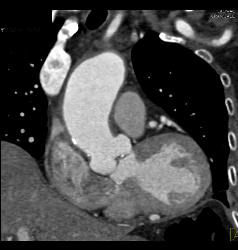

Supravalvular Stenosis and Prior Myocardial Infarction